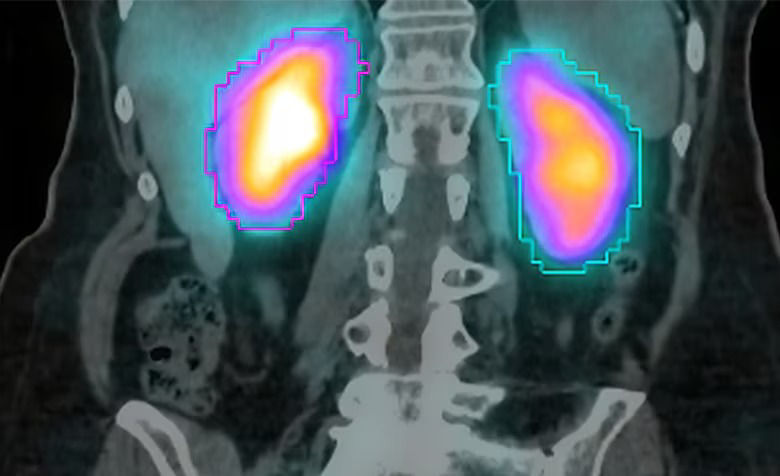

Make StarGuide, with its proven performance, the cornerstone of your theranostics practice as you build up or build out to meet the influx of these advanced procedures. StarGuide, with its optimized collimator design, allows clinicians to perform fast, dual-peak ¹⁷⁷Lu 3D whole body SPECT/CT exams with exceptional lesion detectability and high quantitative accuracy to help you make the personalized care decisions that are at the heart of theranostics. StarGuide is a future-defining catalyst helping SPECT technology push the promise of theranostics forward.

"New SPECT" is a major enabler in Theranostics. With the ability to identify the bio-distribution and perform dosimetry for therapies like 177Lu, pioneering clinicians rely on SPECT to monitor therapy.

StarGuide’s ability to adjust the proximity of the detectors to the patient’s body as closely as possible, and from all necessary angles, leads to remarkable image quality, volume sensitivity⁵, as well as spatial and energy resolutions. The high-energy resolution enables clinicians to perform dual isotope examinations. The native 3D design streamlines workflows, in the pursuit of eliminating the need for additional acquisitions, as is often the case with conventional 2D gamma cameras. For theranostics, StarGuide enabled acquiring vertex to mid-thigh ¹⁷⁷Lu post-therapy SPECT/CT bone scans with 4 bed positions at 3-minutes/bed and a total scan time of 12 minutes.¹ Rapid whole-body scanning time like this is an important factor in helping improve patient comfort and enabling the patient to remain still during the entire exam.